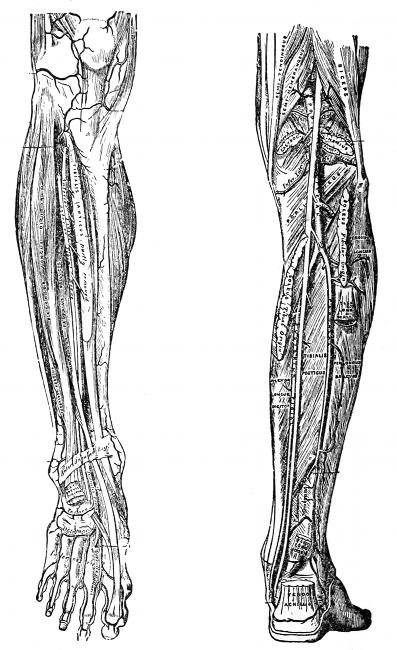

Fig. 4—Lymphatics of

the leg.